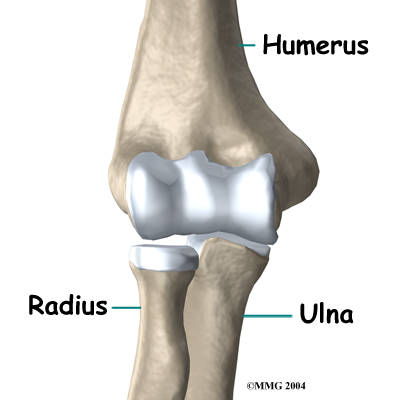

The bones of the elbow are the humerus (the upper arm bone), the ulna (the larger bone of the forearm, on the opposite side of the thumb), and the radius (the smaller bone of the forearm on the same side as the thumb).

The elbow itself is essentially a hinge joint, meaning it bends and straightens like a hinge. But there is a second joint where the end of the radius (the radial head) meets the humerus. The knob on the end of the humerus is called the capitellum. The capitellum fits into the cup-shaped end of the radius, also called the head of the radius, or radial head. This joint is complicated because the radius has to rotate so that you can turn your hand palm up and palm down. At the same time, it has to slide against the end of the humerus as the elbow bends and straightens. The joint is even more complex because the radius has to slide against the ulna as it rotates the wrist as well.